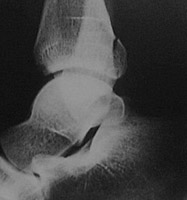

- Click on the image for a larger versionALateral radiograph of the ankle. This shows a fracture of the posterior lip of the tibia.